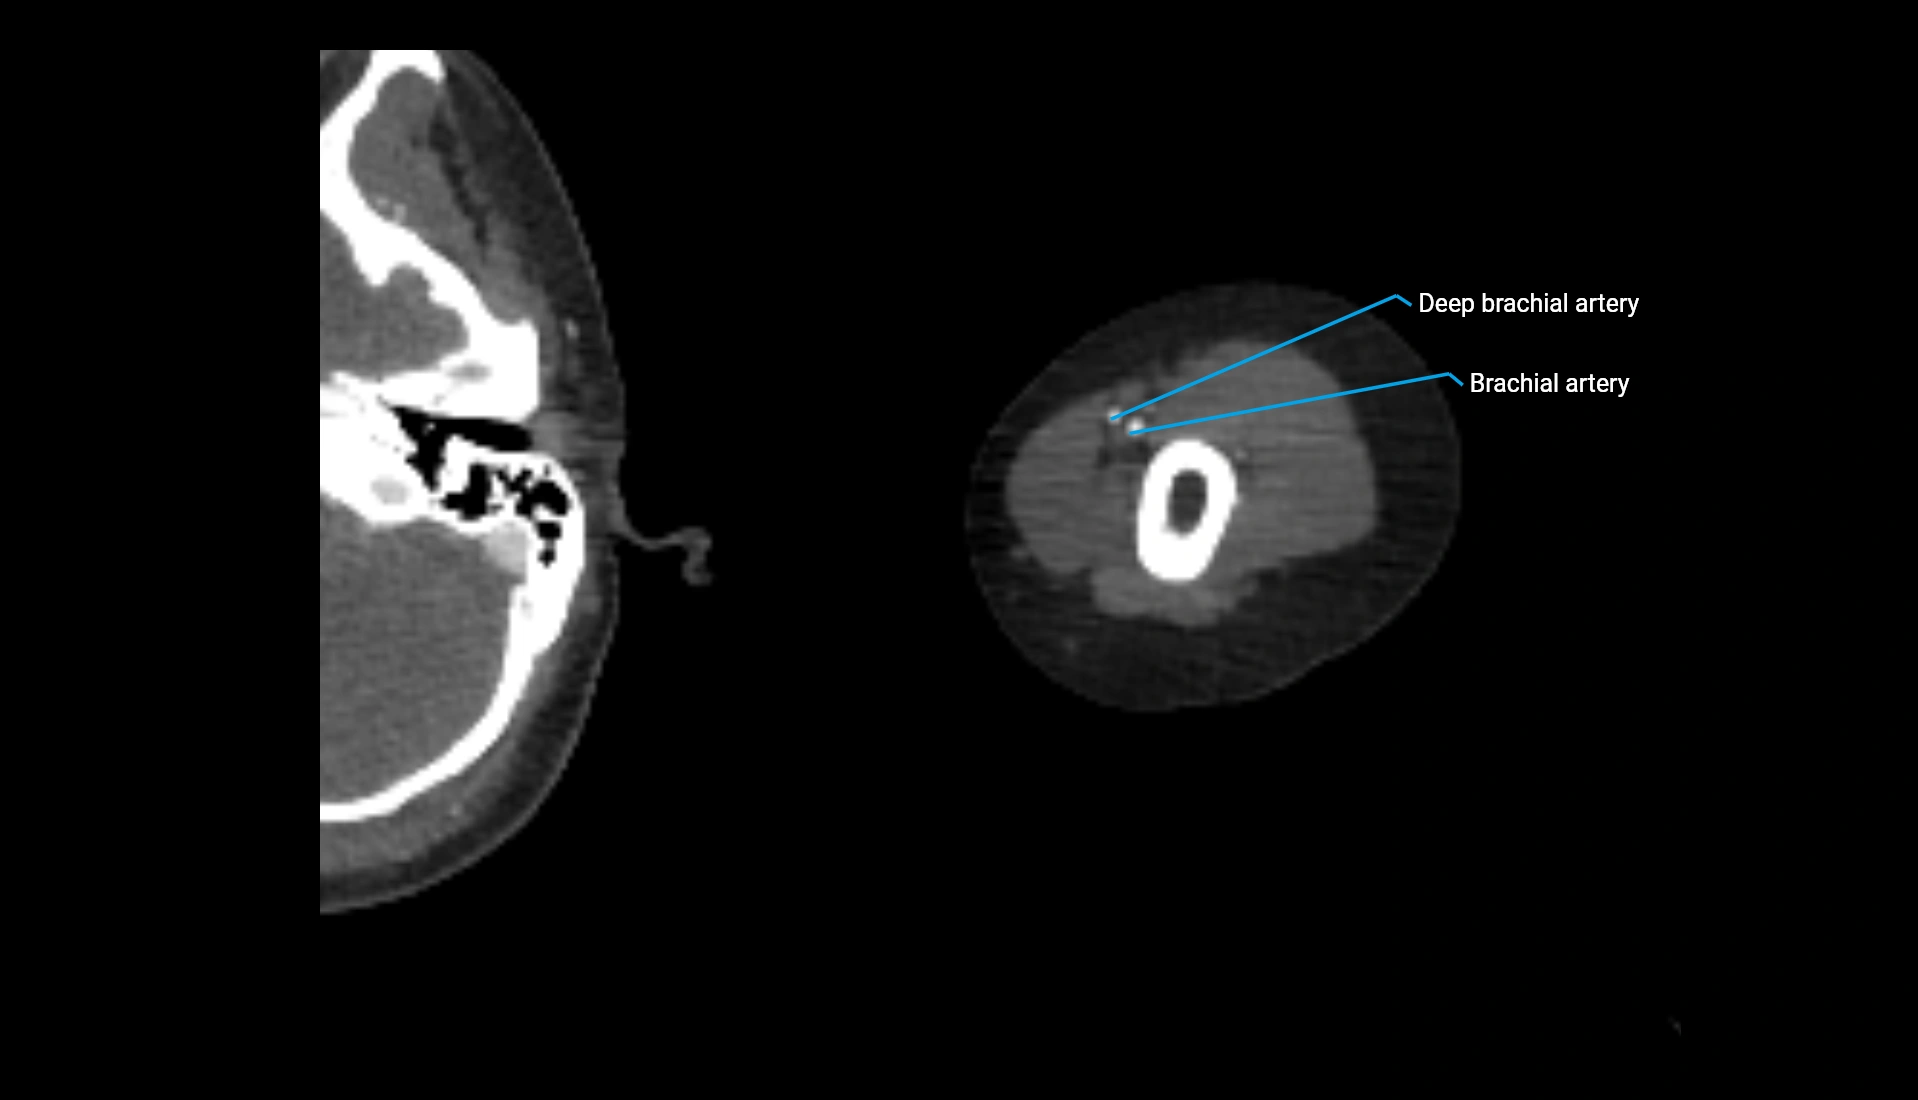

CT Appearance

Non-Contrast CT:

• Cortex: High-density, sharply defined

• Subchondral bone: Dense cancellous matrix

• Articular surface: Smooth concave contour articulating with the capitellum

• Excellent for evaluating bone integrity, alignment, and subtle fractures

Post-Contrast CT:

• Bone: No enhancement

• Joint capsule and synovium: Mild enhancement outlining the joint

• Improves contrast between soft tissues and bony margins

• Useful in detecting subtle joint abnormalities or postoperative changes